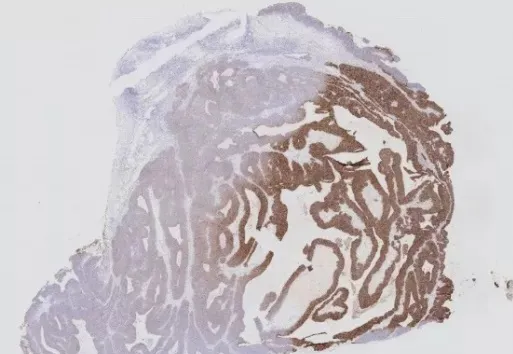

四、邊緣效應(yīng)

干片的原因有動(dòng)作太慢、忘記滴液、滴液流失等,造成非特異性染色,即“邊緣效應(yīng)”(如圖4)。采用DAKO筆或PAP Pen在距離組織邊緣3-4 mm處畫圈,可達(dá)到有效的避免液體流失、提高操作速度的效果。

另外,向清洗緩沖液中加入吐溫20(Tween-20)也是一種防止干片的好方法。500ml PBS磷酸鹽緩沖液,加入2~3滴Tween-20即可。

圖4 邊緣效應(yīng)